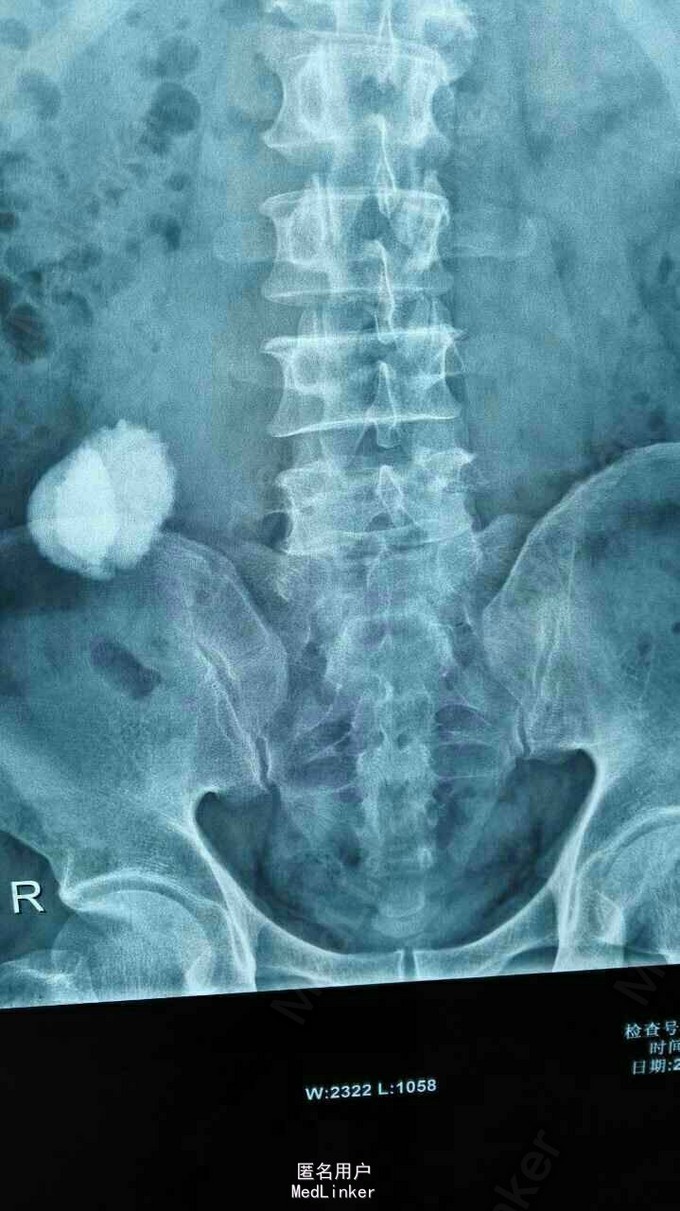

异位肾结石

因反复右侧腹部疼痛5年入院。 5年无诱因出现右侧腹部疼痛,呈阵发性胀痛,无发热,无恶心、呕吐,无尿频、尿急,无肉眼血尿,大便正常,体重无明化。

腹平软,全腹无明显压痛及反跳痛,肠鸣正常,肾区无隆起无叩痛。 辅查,肾功能、血生化均正常。

诊断:右侧异位肾结石并肾积水。 拟行经皮肾镜碎石取石术,但因庙小,患者要求上级医院治疗。